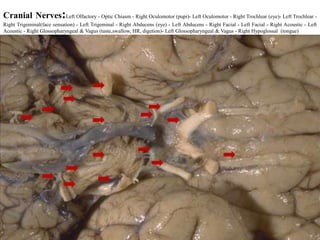

Cranial Nerves:Left Olfactory - Optic Chiasm - Right Oculomotor (pupi)- Left Oculomotor - Right Trochlear (eye)- Left Trochlear -

Right Trigeminal(face sensation) - Left Trigeminal - Right Abducens (eye) - Left Abducens - Right Facial - Left Facial - Right Acoustic - Left

Acoustic - Right Glossopharyngeal & Vagus (taste,swallow, HR, digetion)- Left Glossopharyngeal & Vagus - Right Hypoglossal (tongue)

• #64 Cranial nervesThe brain communicates with the body through the spinal cord and twelve pairs of cranial nerves (Fig. 6). Ten of the twelve pairs of cranial nerves that control hearing, eye movement, facial sensations, taste, swallowing and movement of the face, neck, shoulder and tongue muscles originate in the brainstem. The cranial nerves for smell and vision originate in the cerebrum.

• #66 Left Olfactory - Optic Chiasm - Right Oculomotor - Left Oculomotor - Right Trochlear - Left Trochlear - Right Trigeminal - Left Trigeminal - Right Abducens - Left Abducens - Right Facial - Left Facial - Right Acoustic - Left Acoustic - Right Glossopharyngeal & Vagus - Left Glossopharyngeal & Vagus - Right Hypoglossal -